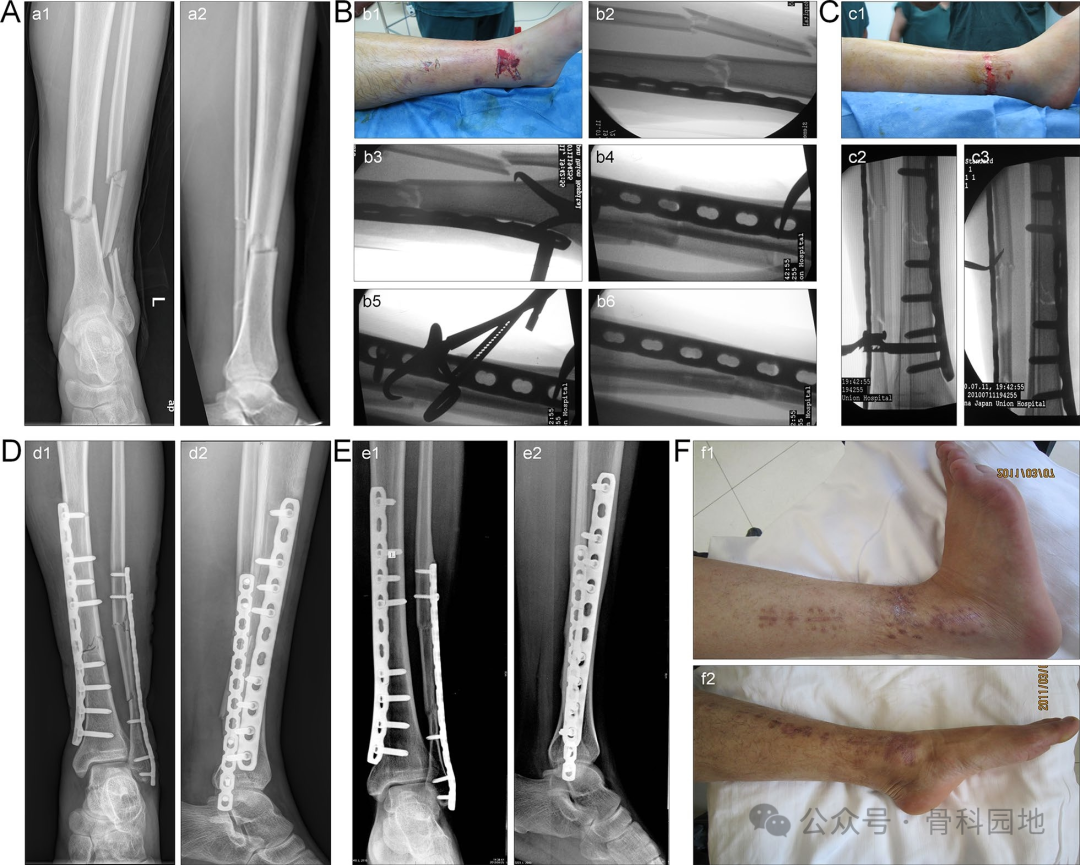

使用MIPO技术。准备一个内侧皮下骨外隧道,然后将钢板植入隧道中。调整位置使钢板紧贴骨表面后,用克氏针或钻头暂时固定靠近切口部位的钢板末端(下图A,B)。使用c臂透视从正位和侧位角度评估钢板的位置以及骨折的位移和角度畸形。通过手动牵引或牵开器复位纠正骨折的缩短和旋转移位。选择合适的点复位钳来维持位置(如下图E、F)。

在短斜骨折和横骨折中,传统的经皮夹持技术通常难以达到满意的复位。然而,当钢板提供正确的对准时,骨折的一端可以首先复位并通过经皮夹持暂时固定。然后,在另一个复位钳的钳夹下完成准确的复位(图)。

前外侧钢板辅助经皮钳夹复位治疗多段骨折。